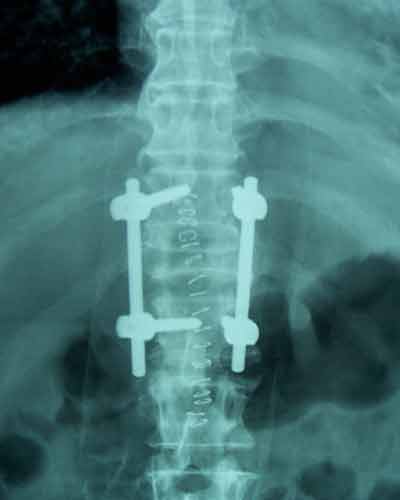

Case:1 Traumatic Fracture L1 with Cauda Equina

60 years old female with one& half months old fracture L1 presented with complete paraplegia with bladder & bowel involvement. She was treated with posterior decompression (Laminectomy), reduction of retroplused fragrant & pedicure screw fixation. Full neurological recovery on 6th day.

Post-op Ap